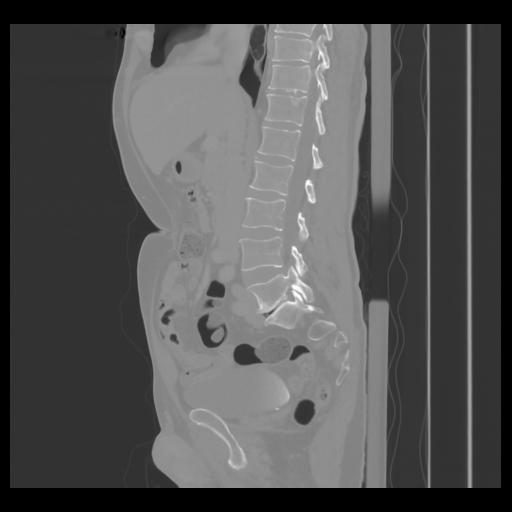

36 CUERPO,CE,Sagittal,3.000,CUERPO,Sagittal,